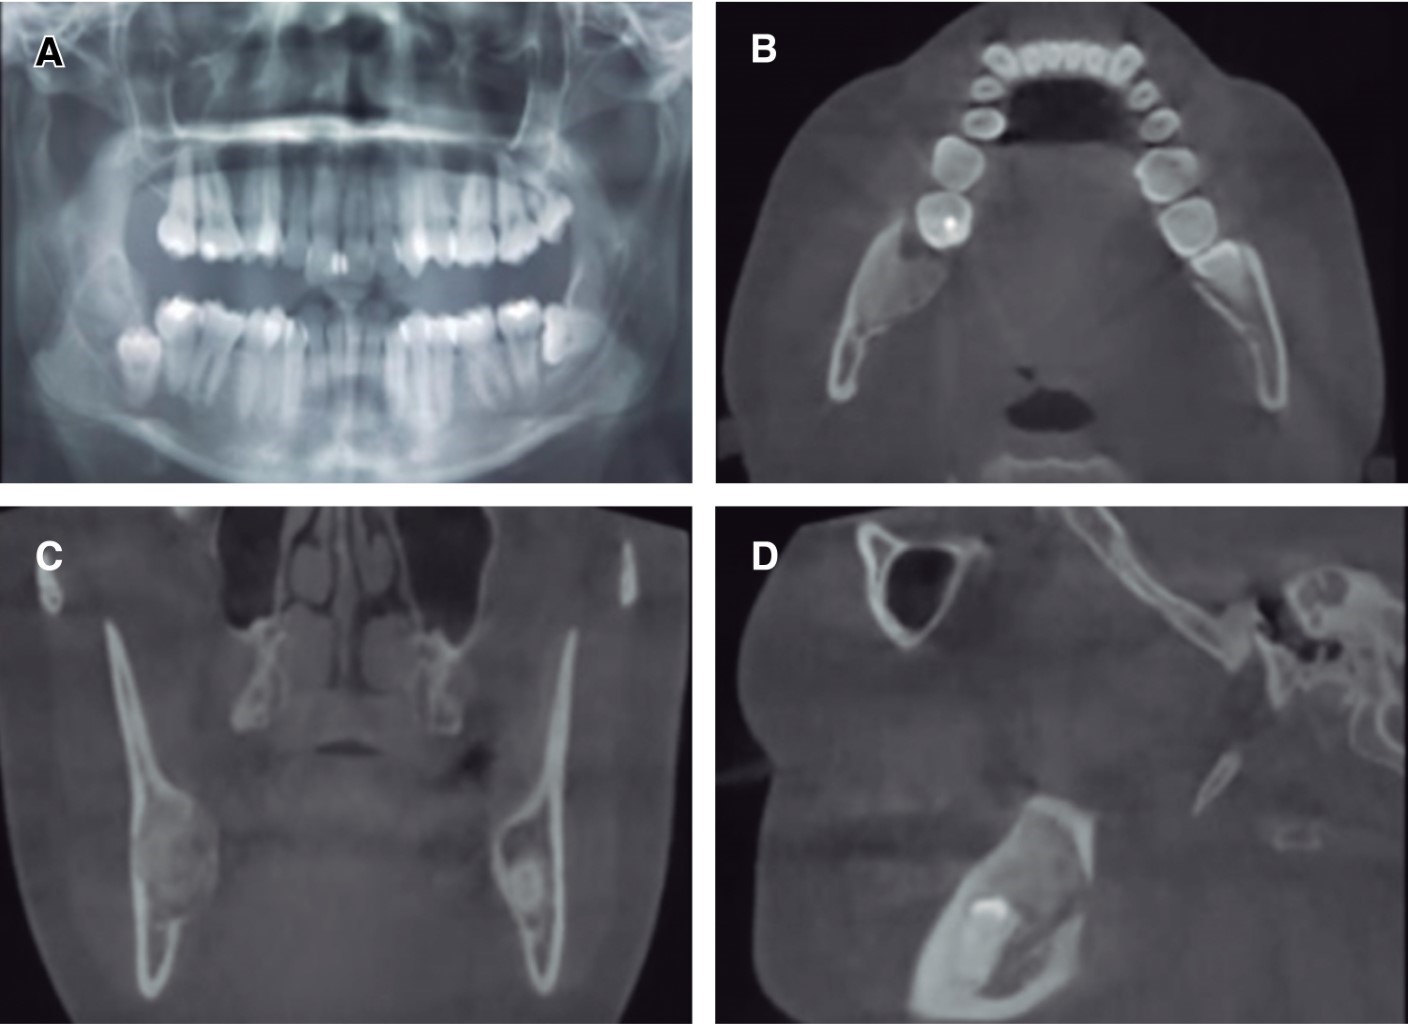

Mujer de 34 años, con antecedentes de hipotiroidismo en tratamiento, es referida desde el Servicio de Especialidades Odontológicas del Complejo Asistencial Barros Luco (SEO) por hallazgo radiográfico en ortopantomografía evaluada en el Centro de Salud Familiar de su comuna. Relata presentar ocasionalmente disestesia de labio inferior de más de un año de evolución. Al examen extraoral, presenta leve asimetría en zona del ángulo mandibular derecho, intraoralmente se aprecia mucosa y encías de aspecto normal, aumento de volumen en zona retromolar derecha de consistencia pétrea y asintomático a la palpación (Figura 1).

En los exámenes imagenológicos, la ortopantomografía describe diente 4.8 semi-incluido en angulación vertical, con lesión de densidad mixta distal a diente 4.8, de 4 × 3 centímetros de extensión, bordes escleróticos y centro radiopaco, sobreproyectado en conducto alveolar inferior. Se solicitó tomografía computarizada en la cual se observó área de densidad mixta, circunscrita de límites definidos, distal a pieza 4.8 semi incluida y anterior a rama mandibular, evidente expansión cortical vestibular y lingual (Figura 2). Se realizó biopsia incisional en pabellón central bajo anestesia general, extrayendo muestra de tejido de consistencia dura y en conjunto se realizó exodoncia de diente 4.8 por proximidad y compromiso con lesión; el acondicionamiento y síntesis de tejidos blandos fue minucioso utilizando plasma rico en fibrina (PRF) para favorecer cicatrización. El estudio histopatológico describe lesión con proliferación de tejido fibroso, presencia de fibroblastos entremezclados en tejido mineralizado tipo cemento, vascularización moderada y ausencia de atipias celulares.

A nivel imagenológico, el FCO presenta variaciones en su densidad dependiendo del estado de maduración y calcificación,3,12 en el caso descrito, la lesión se presentó bien definida, con áreas de densidad mixta en la TC y radiopaca-radiolúcida en la radiografía.